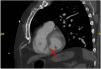

This is the case of a 65-year-old male admitted due to progressive dyspnea of a 20-day history. He is admitted with clinical signs of cardiogenic shock and an unknown panfocal systolic murmur. Complementary tests are performed. The ECG reveals the presence of 1 mm ST-segment depression from V3 to V6 and Q-wave in the inferior wall. Troponin-T levels are 1100 pg/L. The bedside echocardiogram (TTE) performed reveals the presence of right ventricular dilatation with severe tricuspid regurgitation. A coronary computed tomography angiography (CCTA) is, then, performed. The CCTA rules out pulmonary embolism. However, it confirms the presence of ventricular septal rupture (Figs. 1 and 2). A repeat TTE confirms the finding, most likely due to an evolved acute myocardial infarction (Fig. 3). Given the situation of cardiogenic shock, the patient is, then, transferred for veno-arterial extracorporeal membrane oxygenation (ECMO). This case shows the utility of the CT scan to assess complications associated with ischemic heart disease, particularly when the TTE offers diagnostic uncertainties or suboptimal imaging.